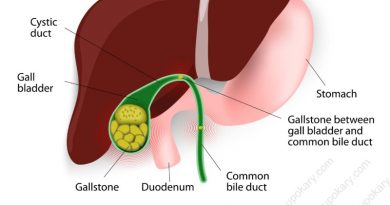

লাইপোমা (lipoma) হল ত্বকের ঠিক নীচে অবস্থিত একটি ফ্যাটি টিউমার। এটি ক্যান্সার নয় এবং সাধারণত ক্ষতিকারক নয়। লিপোমা হল একটি ধীরগতিতে বর্ধনশীল, চর্বিযুক্ত পিণ্ড।

লাইপোমাতে স্পর্শ করলে নরম অনুভূত হয় এবং সামান্য আঙুলের চাপে সহজেই নড়াচড়া করে। চিকিৎসকরা লাইপোমাকে সৌম্য টিউমার হিসাবে বিবেচনা করেন। যার অর্থ হল লাইপোমা অ-ক্যান্সার।

নরম টিস্যু টিউমারগুলোর মধ্যে লাইপোমা হচ্ছে সবচেয়ে সাধারণ। লাইপোমাগুলো সাধারণভাবে ব্যথাহীন। অনেক লাইপোমা ছোট আকারের হয়ে থাকে। সাধারণত ৪০ থেকে ৬০ বছর বয়সে লাইপোমা বেশি দেখা দেয়, তবে শিশুদেরও এটা হতে পারে।

লিপোমা বা লাইপোমা হল একটি গোলাকার বা ডিম্বাকার আকৃতির টিস্যুর পিণ্ড। লিপোমাস শরীরের যে কোনও জায়গায় হতে পারে। লাইপোমাস হল ননক্যান্সার, ফ্যাটি টিস্যু বৃদ্ধি যা আপনার ত্বকের নিচে ধীরে ধীরে বিকাশ লাভ করে। ন্যাশনাল হেলথ সার্ভিস (NHS) অনুসারে এগুলি খুব কমই ক্ষতিকারক এবং সাধারণত চিকিৎসার প্রয়োজন হয় না।